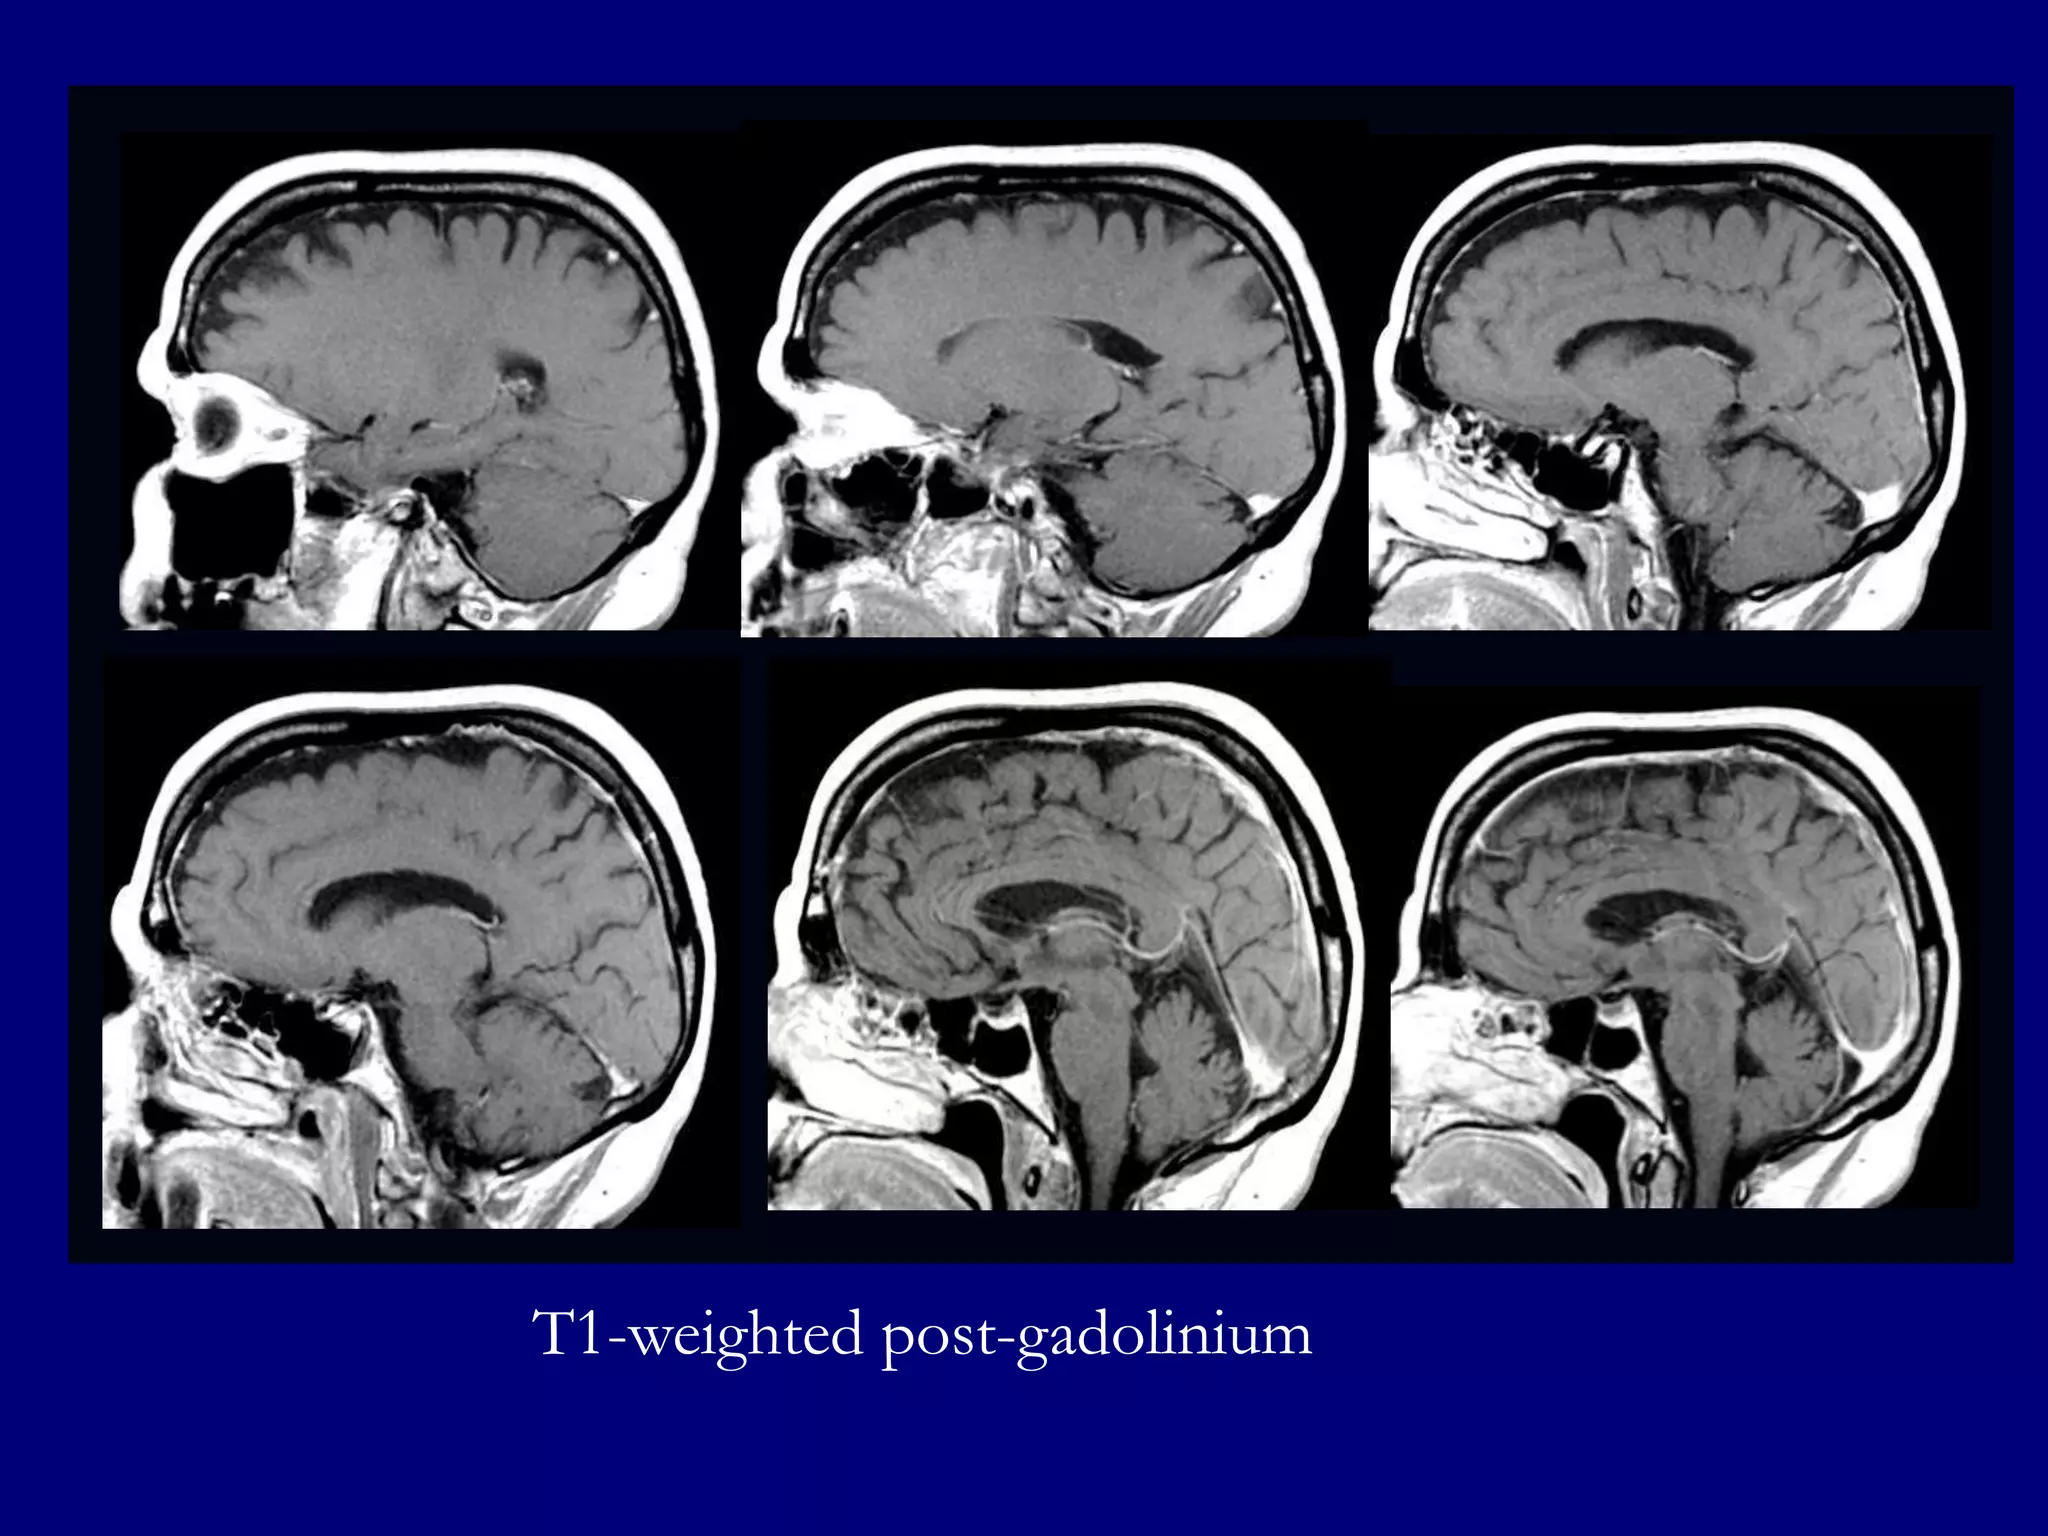

T1-weighted Post-gadolinium images show homogenously enhancing well defined

lesions in left fronto-parietal lobes and enhancement in left cerebellum

MRI

 FLAIR/T2-hyperintense homogenously enhancing

masses in high grade lesions. Enhancement may be

minimal or absent in low grade lesions